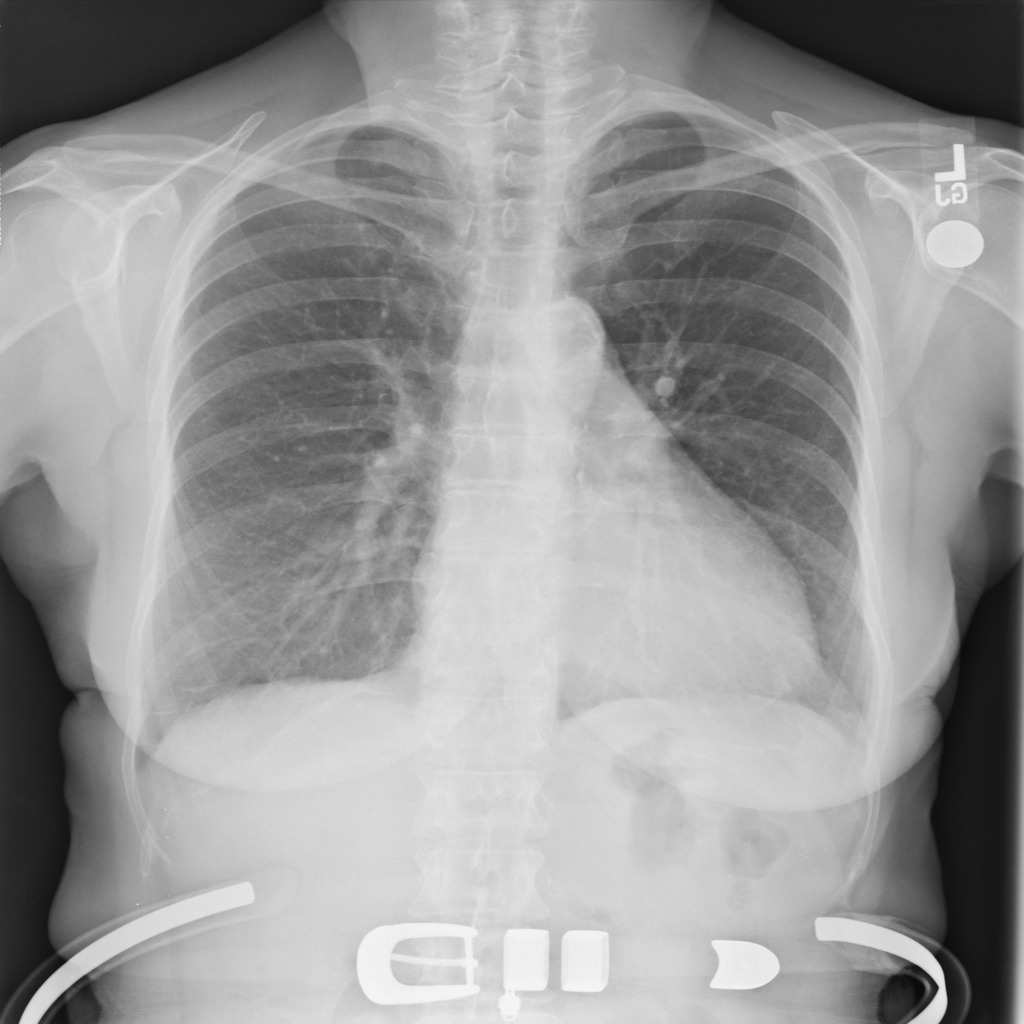

Showing up to 90 reference images for Cardiomegaly.

PAT-4639 · IMG-045Cardiomegaly

PAT-4639 · IMG-045

PA